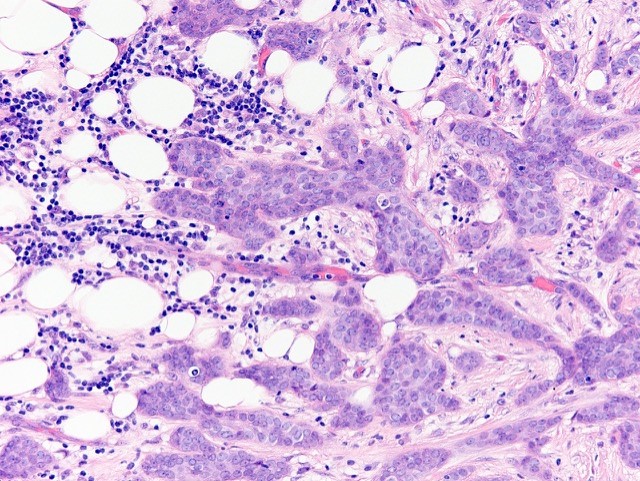

Microscopic (histologic) description

- Histological features of IBC NST vary considerably from case to case and even within the same case

- Margins vary from highly infiltrative, permeating the surrounding tissue, to continuous pushing margins

- Architecture varies from sheets, nests, clusters, cords or individual cells (but lacks the cytomorphological characteristics of invasive lobular carcinoma)

- Tubular formations are prominent in well differentiated tumors but absent in poorly differentiated tumors

- 2 distinct growth patterns exist:

- Large and solid nests or syncytial infiltrative growth pattern with little associated stroma and an expansive growth that compresses the surrounding stroma (e.g., most basal-like breast cancers)

- Tumors characterized by small cancer nests accompanied by marked fibrosis (desmoplastic / scirrhous); this type diffusely infiltrates the surrounding tissue as an irregular shaped spiculated mass

- Often ductal carcinoma in situ (DCIS) (up to 80%)

- In some cases, DCIS is extensive

- Associated DCIS is usually of same nuclear grade as the invasive carcinoma

- Angiolymphatic invasion in 35%; differs from tissue retraction because:

Microscopic (histologic) images

Contributed by Julie M. Jorns, M.D., Kristen E. Muller, D.O., Gary Tozbikian, M.D. and Emad Rakha, M.D.